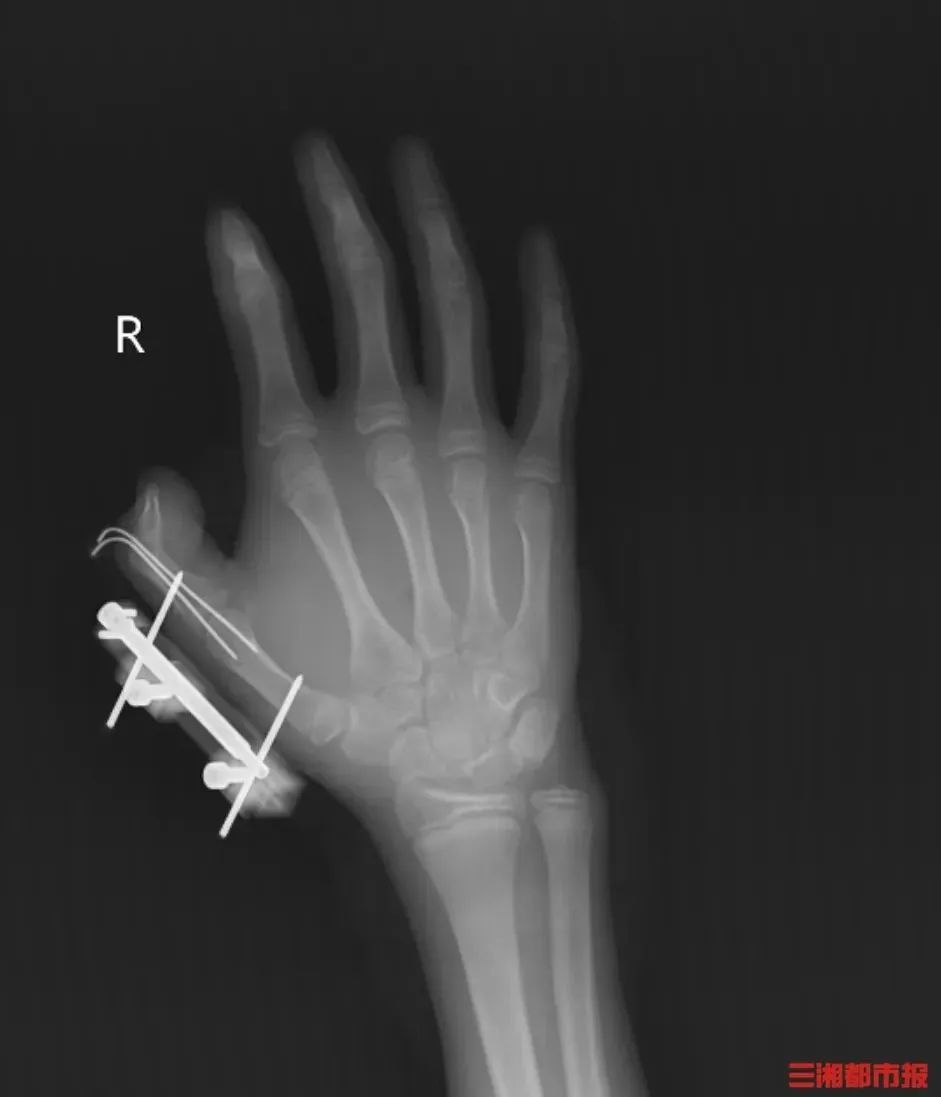

突然,密封袋里的干冰发生爆炸,维维的右手瞬间鲜血直流,拇指虎口处被撕开一道约10厘米的伤口,深可见骨,肌肉组织断裂外露,还伴随着拇指骨折、关节脱位,整个拇指完全失去知觉。

见状,家人赶紧带他到当地医院包扎,随后紧急转往湖南省人民医院手足显微外科。经治疗,维维的拇指保住了,但后续还需长期康复训练,才能慢慢恢复手部精细动作功能。